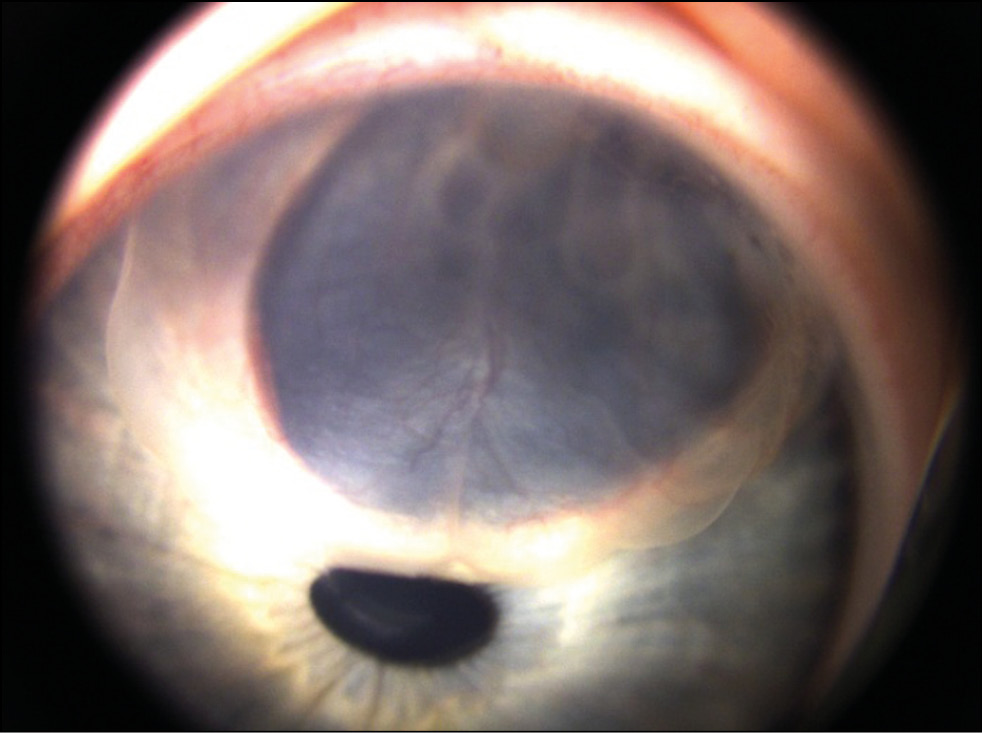

Пациент Г., 3 года. В марте 2020 года на плановом осмотре по месту жительства выявлено пигментное новообразование радужки левого глаза. Больной направлен в НМИЦ глазных болезней им. Гельмгольца (далее — Центр). На левом глазу определено предметное зрение. При осмотре у пациента на левом глазу выявлено пигментированное новообразование зрачкового края радужки (рис. 2). Учитывая размеры новообразования и распространение на оптическую зону было рекомендовано проведение иридэктомии, которая была выполнена в ноябре 2020 г.

Рис. 2. Киста пигментного эпителия зрачкового края радужки.

По данным оптической когерентной томографии у пациента имеется овальное кистовидное образование, исходящее из тканей радужки с гиперрефлективной капсулой и гипорефлективным содержимым (рис. 3).

Рис. 3. Оптическая когерентная томография радужки OS. Кистовидное образование с гиперрефлективной капсулой и гипорефлективным содержимым.

Гистологическая картина соответствовала диагнозу «киста пигментного эпителия радужки». На контрольном осмотре в июне 2021 г. отмечен благоприятный анатомический и функциональный результат.